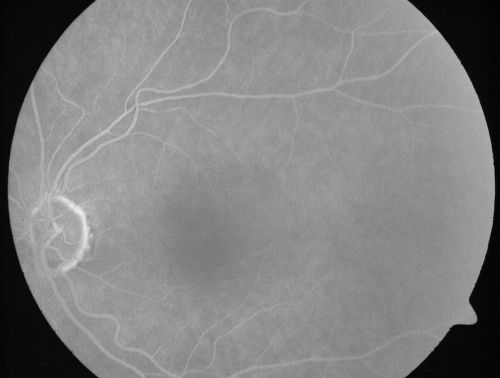

Microaneurysms from Ocular Ischemic Syndrome (non-diabetic) Right Eye - Left eye CRAO 1 year ago

66-year-old woman lost vision in the left eye from a central retinal artery occlusion 1 year ago. Vision OD is fine. OD 20/25, OS 20/50

Ocular Ischemic Syndrome - Microaneurysms right eye (fellow eye old CRAO)